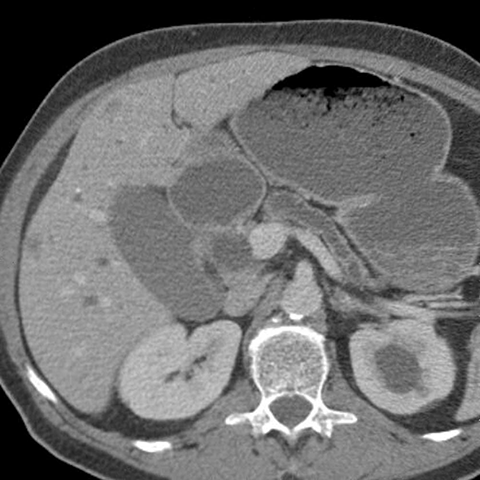

56 year-old male presents with painless jaundice [2 of 7]